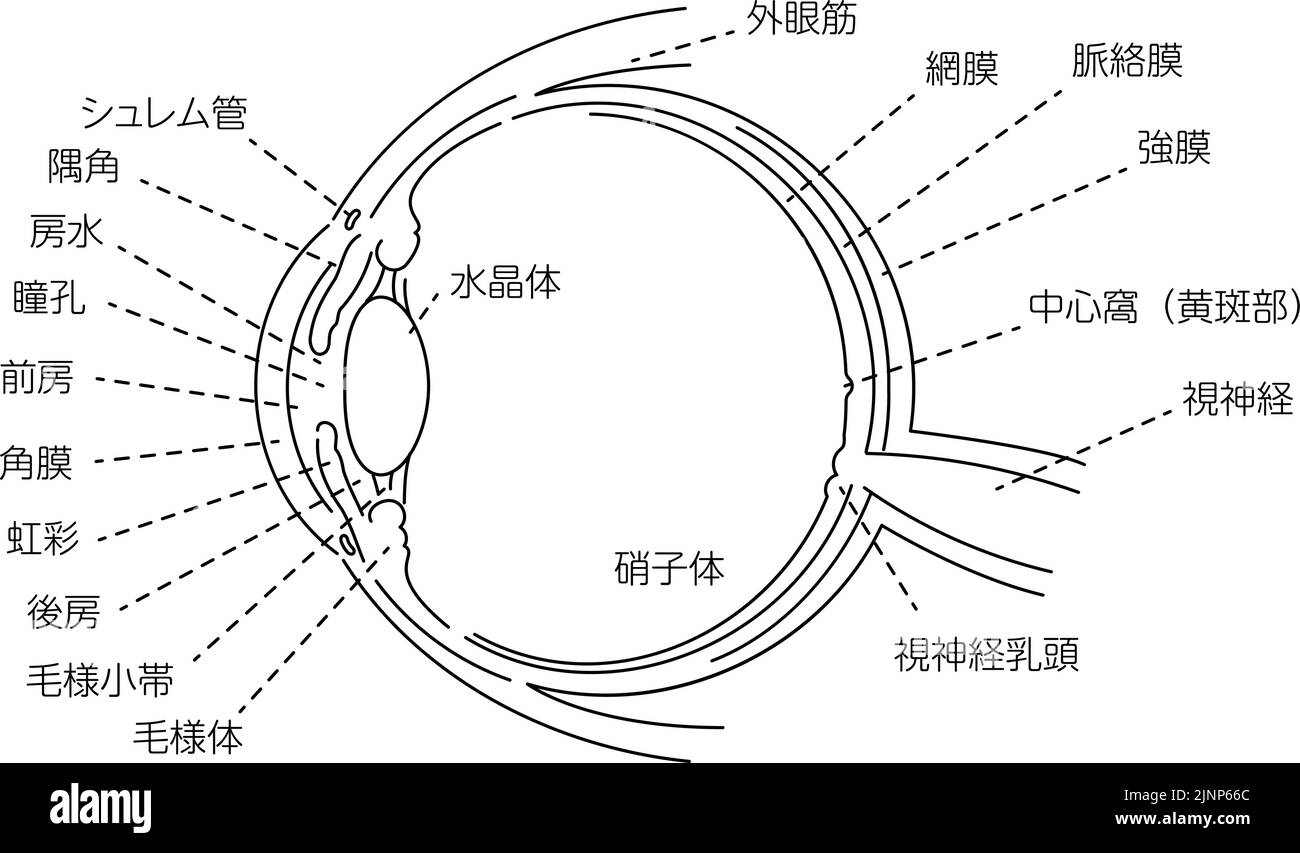

Diagrammatic illustration of the eye (line drawing) Stock Vectorhttps://www.alamy.com/image-license-details/?v=1https://www.alamy.com/diagrammatic-illustration-of-the-eye-line-drawing-image478074574.html

Diagrammatic illustration of the eye (line drawing) Stock Vectorhttps://www.alamy.com/image-license-details/?v=1https://www.alamy.com/diagrammatic-illustration-of-the-eye-line-drawing-image478074574.htmlRF2JNP4YX–Diagrammatic illustration of the eye (line drawing)

Illustration of the eye - Translation: Schlemm's canal, corner angle, aqueous humor, pupil, anterior chamber, cornea, iris, posterior chamber, ciliary Stock Vectorhttps://www.alamy.com/image-license-details/?v=1https://www.alamy.com/illustration-of-the-eye-translation-schlemms-canal-corner-angle-aqueous-humor-pupil-anterior-chamber-cornea-iris-posterior-chamber-ciliary-image478075540.html

Illustration of the eye - Translation: Schlemm's canal, corner angle, aqueous humor, pupil, anterior chamber, cornea, iris, posterior chamber, ciliary Stock Vectorhttps://www.alamy.com/image-license-details/?v=1https://www.alamy.com/illustration-of-the-eye-translation-schlemms-canal-corner-angle-aqueous-humor-pupil-anterior-chamber-cornea-iris-posterior-chamber-ciliary-image478075540.htmlRF2JNP66C–Illustration of the eye - Translation: Schlemm's canal, corner angle, aqueous humor, pupil, anterior chamber, cornea, iris, posterior chamber, ciliary